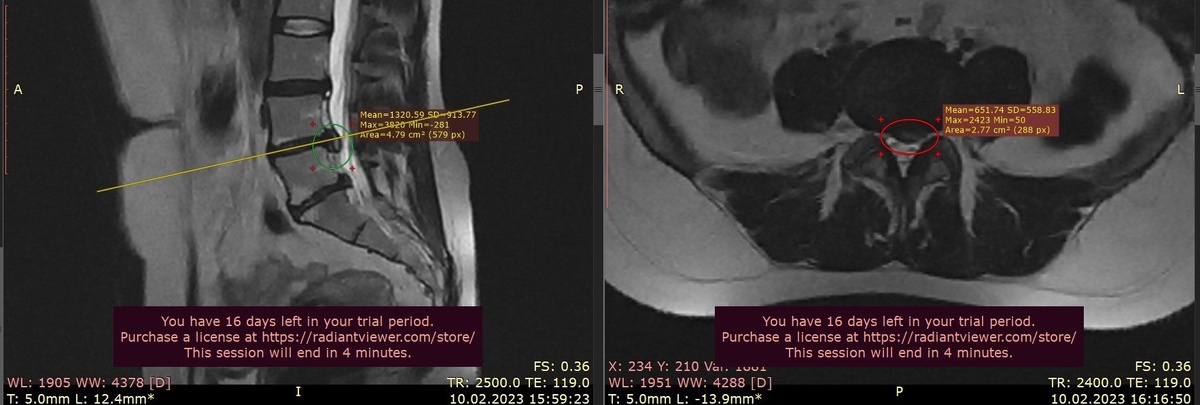

Грыжа с начала обострения увеличилась ( первый снимок), а нервная система стала переходить в состояние гиперчувствительности.

📍 Через 4 месяца на МРТ( второй снимок) — значительное уменьшение грыжи.